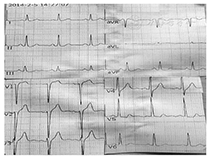

患者 男,43岁,因"反复胸前区疼痛约10 h,加重约3 h"入院。患者2014年2月5日早晨8: 00左右无明显诱因突然出现胸前区、上腹部阵发性疼痛,疼痛位置不固定,向背部放射,伴有胸闷,症状数分钟后能自行缓解,但症状反复发作,当日13: 00来我院诊治,14: 05查丙氨酸氨基转移酶(ALT) 25 U/L(正常值9~ 52 U/L)、天冬氨酸氨基转移酶(AST) 33 U/L(正常值15~ 46 U/L )、乳酸脱氢酶(LDH) 442 U/L(正常值313~ 618 U/L)、肌酸激酶(CK) 71 U/L(正常值30~ 170 U/L )、肌酸激酶同工酶(CK-MB) 20 U/L(正常值0~ 16 U/L)。患者14: 27胸痛间歇期查十二导联心电图示下侧壁导联ST段改变(图1),后患者疼痛有所好转,拟诊腹痛待查,不排除冠心病、心绞痛,给予麝香保心丸后患者离院。15: 00左右患者疼痛加重,剑突下疼痛明显,症状持续不缓解,阵发性加剧,伴有恶心、呕吐、出汗,无晕厥、心悸、呼吸困难,收入院进一步诊治。患者平素吸烟,每天约吸1包烟,否认高血压、糖尿病病史。查体:血压154/109 mmHg (1 mmHg= 0.133 kPa),两肺未闻及干、湿性啰音,心率92次/min,律齐,无杂音,腹平软,上腹部轻压痛,无反跳痛,未触及包块,肝脾肋缘下未触及,Murphy征阴性,肝肾区无叩击痛,双下肢无水肿。胸部X线片无异常。18: 25十二导联心电图无异常(图2)。18: 26查ALT 28 U/L、AST 19 U/L、LDH 433 U/L、CK 83 U/L、CK-MB 16 U/L,血糖、肾功能、血淀粉酶、凝血功能无异常。给予吸氧、严密监护、抗血小板聚集、扩张冠状动脉等处理。胸部、腹部增强CT未见胸腹部异常情况,无主动脉夹层形成。患者症状缓解不明显。22: 30查ALT 27 U/L、AST 36 U/L、LDH 431 U/L、CK 289 U/L、CK-MB 58 U/L,肌钙蛋白T 253 ng/L,血淀粉酶正常。次日0: 10十八导联心电图正常(图3, 图4)。诊断为冠心病、急性心肌梗死、心功能Killip 1级,行冠状动脉造影检查:左前降支近中段狭窄30%,对角支无狭窄;左主干无狭窄;右冠状动脉无狭窄,左回旋支近段完全闭塞;各血管间未见明显的侧支循环(图5)。手术中发现左回旋支近段严重固定狭窄并急性闭塞,予回旋支植入2枚药物支架。数天后患者病情好转出院。